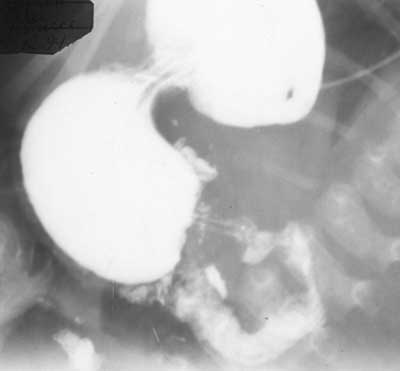

Врожденный пилоростеноз.

Рис. 3. Больной Г., 1,5 мес. Врожденный пилоростеноз. Симптом «параллельных линий». Распределение контраста по тонкой кишке мелкими порциями.